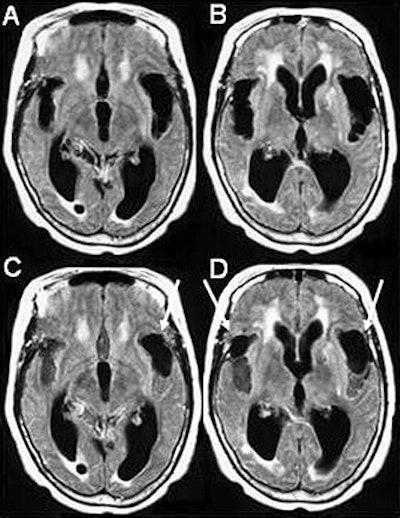

![]() |

| A simple regression analysis between the SPECT images for each subject (and condition) and the NPH scores showed a positive relationship in Brodmann's area 32, corresponding to the anterior cingulate, and the frontal part of the left lobule of the insula of Reil. Image shows two areas most related to clinical improvement from regression analysis. Reprinted with permission from the Society of Nuclear Medicine. Mataró, M; et al, "Postsurgical Cerebral Perfusion Changes in Idiopathic normal pressure hydrocephalus: A Statistical Parametric Mapping of Study of SPECT Images" (J Nucl Med 2003; 44:1884-1889, Fig. 3, p. 1888). |